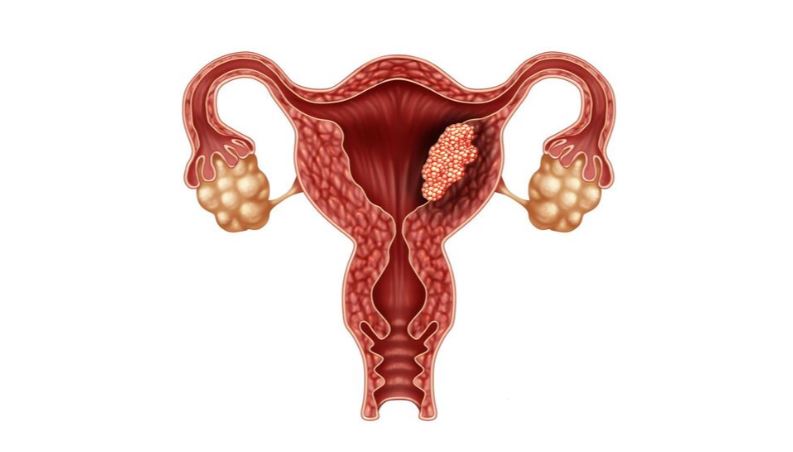

The aim of the procedure is to allow women with absolute uterine factor infertility to have a baby. Absolute Uterine factor infertility is caused due to congenital or surgical absence of the uterus or the presence of a non-functional uterus.

Uterus with its blood supply will be removed from the donor and transplanted to the recipient through the microvascular anastomosis. Before performing the transplant surgery; the recipient should undergo controlled ovarian hyperstimulation and egg collection before the transplant surgery.